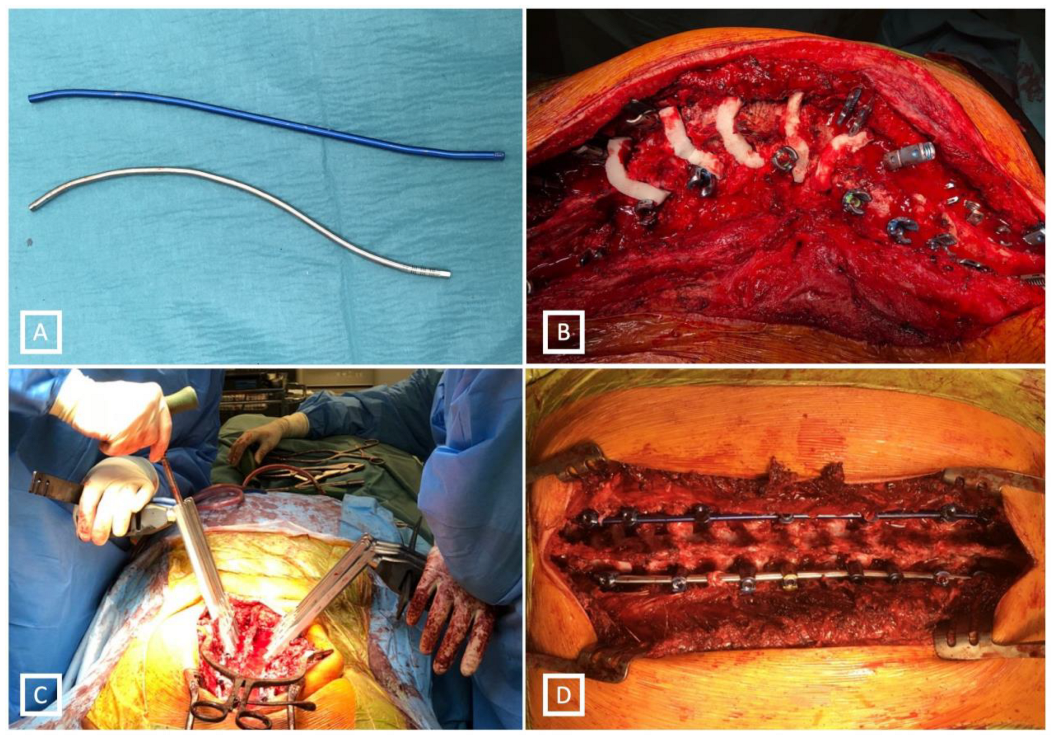

2. Material and Methods